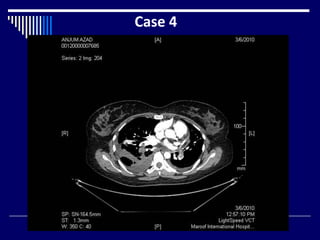

Case 4

Findings

CTPA (1)

Filling defects in Bilateral pulmonary arteries (2)

Bilateral pleural effusions (2)

Soft tissue opacity right lung (1)

Dx : Pulmonary Embolism (3)

What Next = Doppler scan of lower limbs (1)